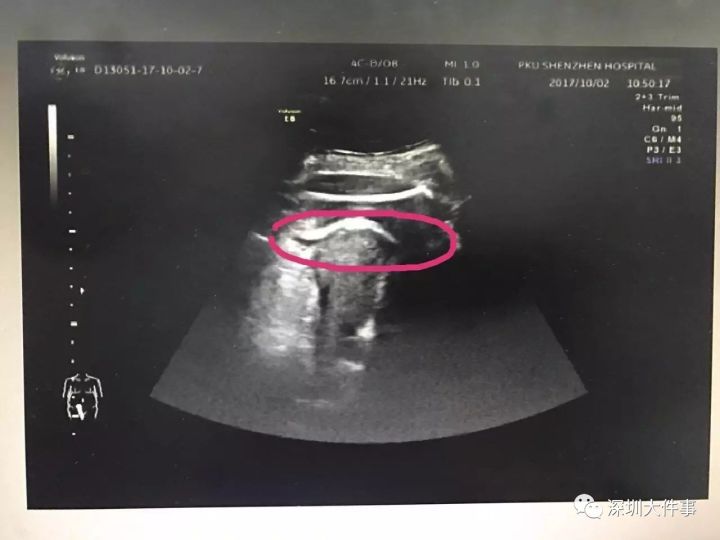

医生初步怀疑患者子宫破裂,当即安排做了B超。检查发现,胎儿的一条腿“踢破”了子宫,进入了腹腔,大腿根正卡在子宫壁上!

▲红色圆圈处是胎儿的腿,已经伸到子宫壁外

医生追问患者病史,原来张女士2016年做过子宫肌瘤剔除术,术后半年就怀孕了。不到2分钟B超检查,仅凭有限病史,医生快速作出诊断:高度怀疑为疤痕子宫破裂。